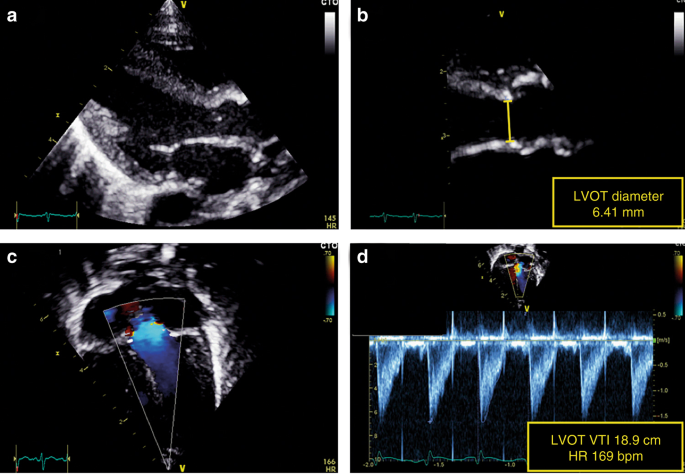

LVO equals the SBF in the absence of ductal shunting. LVO tract diameter is usually measured from the parasternal long-axis view atend-systole (see Fig. 3).28 Variations in diameter location (sub-valvular region, hinge points of the aortic valve, or start of the ascending aorta) and method of diameter measurement (2D or M mode, leading edge or trailing edge) occurs in the literature.29 Variations also exist in VTI acquisition, both in Doppler method (PW or CW) and transducer position (apical, subcostal, or suprasternal). We recommend that diameter measurements should be performed at the hinge points of the aortic valve at end-systole. VTI in the LV outflow tract should be assessed by PW Doppler in the apical five-chamber view or apical long-axis view with the sample volume just below the aortic valve.30 We recommend 2D freezing during PW Doppler recordings to obtain a smooth VTI envelope for more exact tracing of the signal.

Assessment of left ventricular output (LVO). LV outflow tract diameter is measured from the parasternal long-axis view (a). The diameter measurement should be performed at the hinge points of the aortic valve at end-systole (b). The velocity time integral (VTI) in the LV outflow tract should be assessed in the apical five-chamber view or apical long-axis view using pulsed-wave Doppler with the sample volume just below the aortic valve (c). The pulsed wave Doppler recording is paused to obtain a smooth VTI envelope for exact tracing of the signal (d)